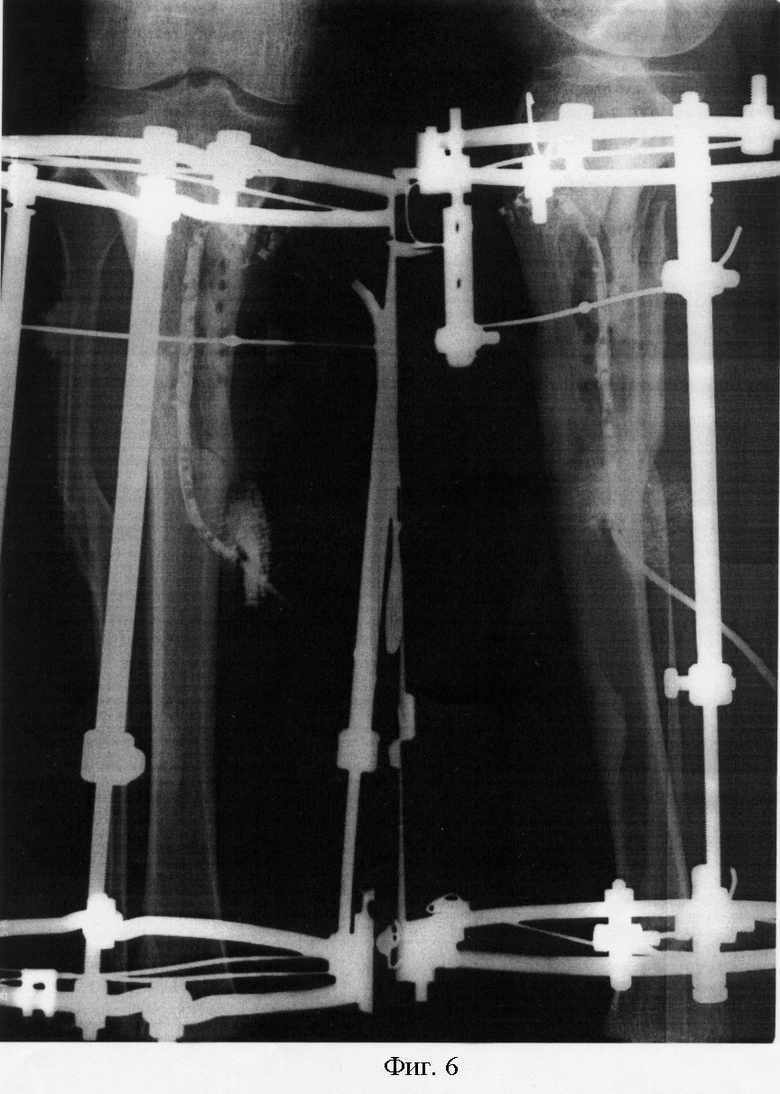

Рентгеновские снимки посттравматического остеомиелита челюсти: Медицинские случаи

Раздел: Образы вокруг